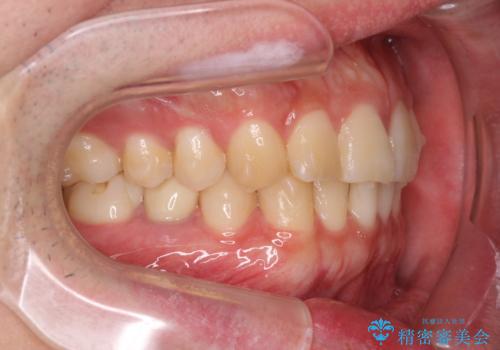

前歯のがたつきをなおしたい マウスピース矯正

- 気になる前歯のがたつきをきれいにしたい。と矯正治療を希望され来院されました。

大きな歯列の乱れはないため、倒れ込んでいる奥歯の傾きの改善、前歯のがたつきを改善する治療を計画します。

見た目が良くなっただけではなく、歯ブラシがしやすくなった!と治療後の歯並びに喜んでいただくことができました。